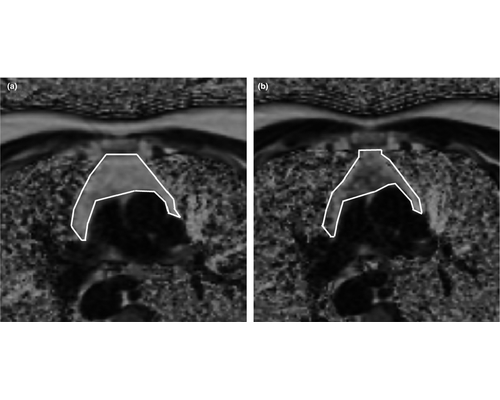

9.我国自主研发临床全数字PET/CT装备获准进入市场

华中科技大学谢庆国教授团队发明的全数字PET/CT,已于2019年5月31日通过国家药品监督管理局注册审批,获得市场准入和对外销售资质。这意味着国产全数字PET打破国际技术垄断,我国高端医疗仪器开发取得重大突破。

PET是正电子发射断层成像的简称,是继超声、CT和核磁共振之后当今的尖端医学影像技术,在恶性肿瘤、神经系统疾病、心血管疾病等重大疾病早期诊断、疗效评估、病理研究等方面,具有极大应用价值。